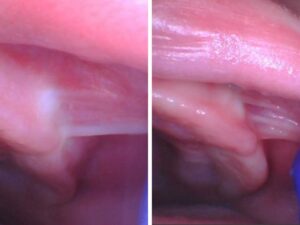

The study surveyed 466 healthcare providers experienced in evaluating and managing oral restrictions. A staggering 87% indicated that they assess buccal restrictions using methods such as finger sweeps, visual inspections, and tissue blanching. The study also found that both objective and subjective findings are crucial for diagnosis. Approximately 70% of providers release buccal-ties simultaneously with tongue-ties, and nearly 77% recommend post-operative stretches for optimal healing.

The study mentions the effectiveness of using dental lasers, such as a CO2 laser, for treating buccal-ties. LightScalpel’s CO2 laser technology offers a quick procedure with minimal bleeding and excellent hemostasis, making it a preferred choice among healthcare providers.